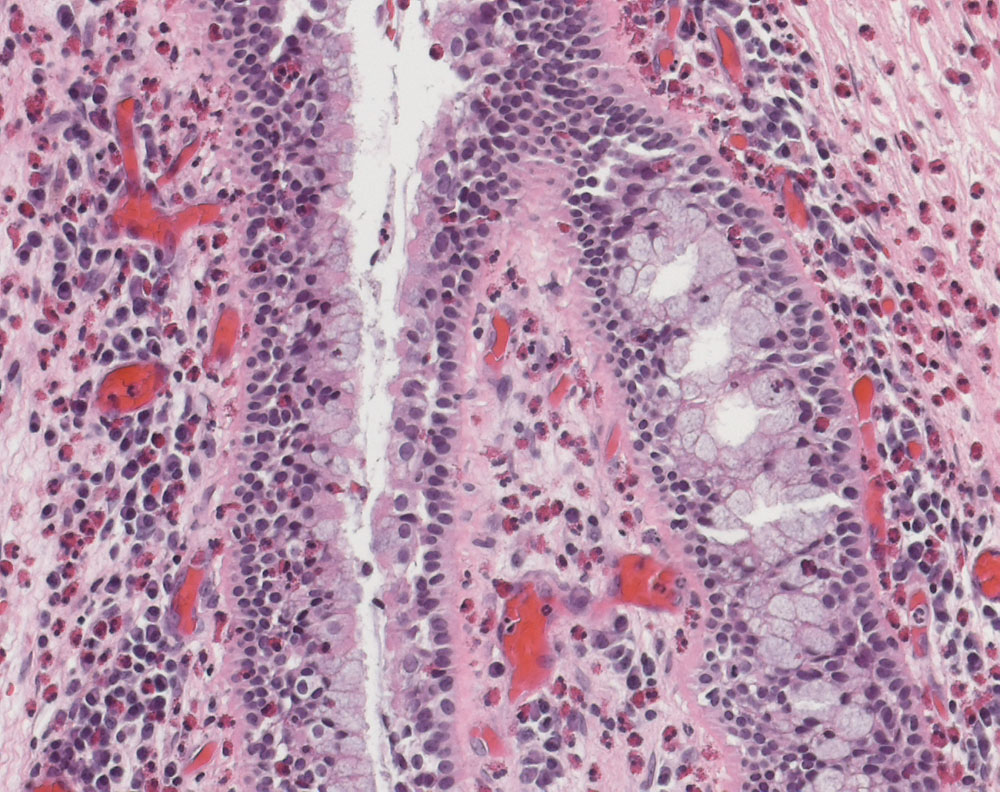

Inflammatorischer (otischer) Polyp des Mittelohrs

Von Zylinderepithel mit Becherzellen ausgekleidete Schleimhaut mit dichten Infiltraten von Plasmazellen und eosinophilen Granulozyten.

Inflammatorische/otische Polypen entstehen im Rahmen einer chronischen Otitis media oder einer Samster's Triade (chronische Rhinosinusitis mit Nasenpolypen, Aspirinsensitivität und Asthma bei einem nicht atopischen Patienten). Bis zu 35% sind assoziiert mit einem Cholesteatom.

Histologie

200